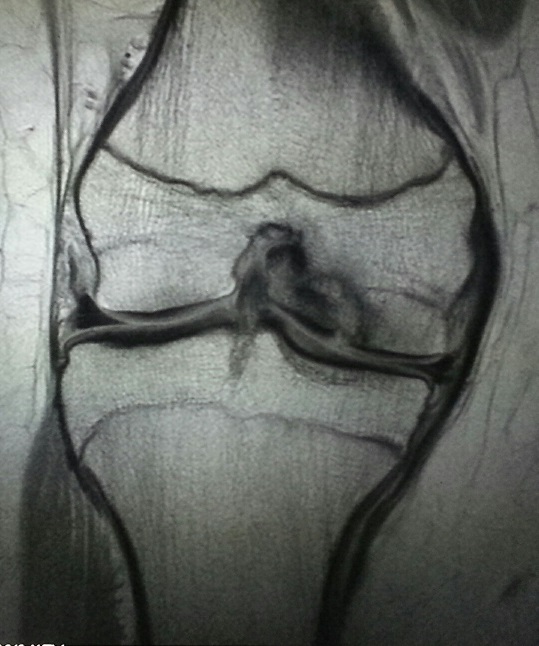

Figure 1. Frontal radiograph of the right knee.

Frontal and lateral radiographs of the right knee demonstrate a region of irregularity of the lateral aspect of the medial femoral condyle at the weight-bearing surface. There is lucency

between this osseous irregularity and the parent bone. On the lateral view, there is a joint effusion. This is the classic appearance and location for osteochondrosis dessicans.

The frontal radiograph of the knee demonstrates cortical irregularity of the lateral aspect of the medial femoral condyle. Upon closer inspection of the region, there is sclerotic region (of increased density) with a band of lucency about it. Increased sclerosis is identified in the adjacent medial femoral condyle. The abnormal region of bone is also small in size compared to what one would expect.

Figure 3. T1 weighted MRI of the right knee in the coronal plane.